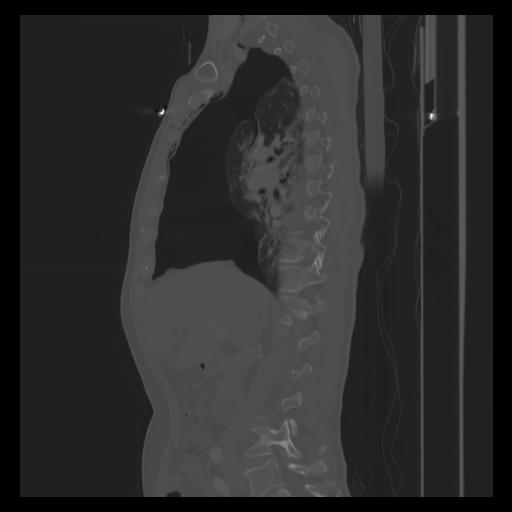

30 CUERPO,CE,Sagittal,3.000,CUERPO,Sagittal,